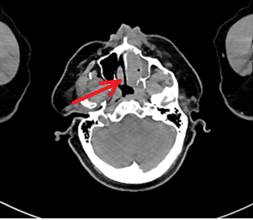

Пациент 1. Мужчина, 69 лет. По данным обследования установлен диагноз ДВКЛ стадии IIАE: выявлено поражение левой верхнечелюстной пазухи, ячеек решетчатой кости слева и левой орбиты (рис.1, А). ИГХ-исследование биоптата мягких тканях левой верхнечелюстной пазухи показало: CD20+, Bcl-2+, MUM1+/-, Bcl-6-/+, CD10-, CD23-, Cyclin D1-, индекс пролиферативной активности Ki-67 – 80%. На основании профиля экспрессии (CD10-, Bcl-6-/+, MUM1+/-) опухоль отнесена к non-GCB подтипу. Сопутствующая патология: ишемическая болезнь сердца, гипертоническая болезнь III стадии, хроническая болезнь почек (ХБП) 3А стадии (расчетная скорость клубочковой фильтрации, рСКФ, по формуле CKD-EPI – 48 мл/мин/1,73 м²), ожирение III степени. Перед началом терапии уровень лактатдегидрогеназы (ЛДГ) был в пределах нормы (167 Е/л). После проведения шести курсов терапии по схеме R-CHOP (ритуксимаб, циклофосфамид, доксорубицин, винкристин, преднизолон), по данным ПЭТ/КТ зарегистрирован полный метаболический ответ.

Пациент 2. Мужчина, 63 лет. По результатам обследования установлен диагноз ДВКЛ IIА стадии: выявлено поражение правой небной миндалины и лимфоузлов шеи (рис.1, Б). ИГХ-исследование биоптата лимфоузла шеи справа показало: CD20+, Bcl-2+, Bcl-6+/-, MuM1+, CD10-, c-MYC+/-, индекс пролиферации Ki-67 – ~95%. Морфологическая и иммунофенотипическая характеристика соответствовала ДВКЛ высокой степени злокачественности (High-grade). Сопутствующая патология: ишемическая болезнь сердца, хроническая сердечная недостаточность I стадии (ФК 2), сахарный диабет 2 типа, ХБП смешанного генеза 4 стадии (СКФ по CKD-EPI-27,1 мл/мин/1,73 м²). Перед началом терапии уровень ЛДГ был в пределах нормы (200 Е/л). Пациенту была назначена терапия первой линии по схеме R-CHOP. После проведения первого курса химиотерапии было отмечено раннее прогрессирование заболевания. В связи с резистентностью опухоли и развитием полиорганной недостаточности пациент скончался.

Рис.1. Аксиальный срез компьютерной томографии. Красной стрелкой отмечена область патологического очага. А – пациент 1; Б – пациент 2.

Примечание: составлен авторами по результатам данного исследования